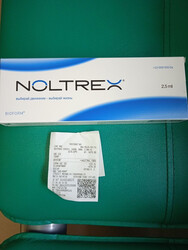

Само колено не ахти, разрушается. В него была введена половина дозы препарата

Noltrex (чек прилагается).

беспокоит. В него введена 2ая половина препарата.

Действие препарата от года до 5 лет. Можно им поддерживать. Контрольный рентген сделают, когда приедет в приют. Ограничение подвижности 3 нед, потом можно в вольер.

6 276 ₽ куплен Noltrex